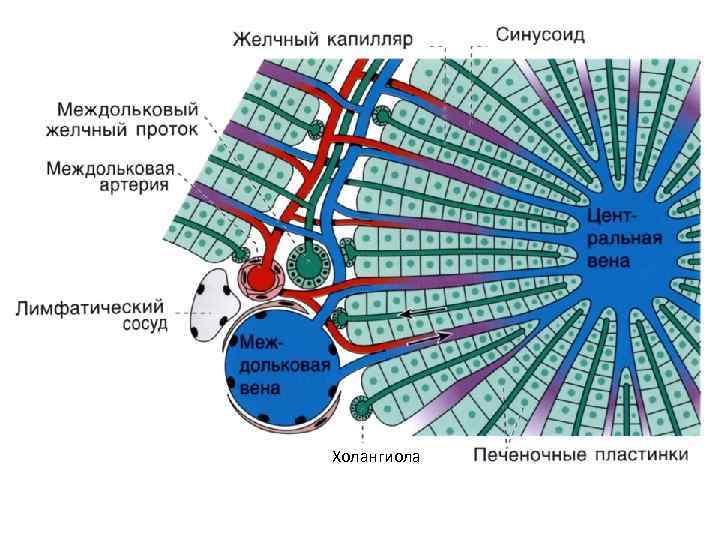

капилляр

капилляр

Холангиола

CV- центральная вена BD- желчные протоки * - синусоидные капилляры

Междольковый желчный проток 1 - просвет желчного протока, 2 - ядра эпителиоцитов, 3 - микроворсинки, 4 - десмосома, 5 - плотные контакты, 6 - базальная мембрана

Синусоидный капилляр печени 1 -эндотелий с порами, 2 - пространство Диссе

Желчный капилляр печени 1 - ядро, 2 -митохондрия, 3 - лизосома с желчными пигментами, 4 - желчный капилляр

Желчный капилляр

1 - зона оптимального кровоснабжения, 2 - зона умеренного кровоснабжения, 3 - зона наихудшего кровоснабжения (наиболее уязвима при интоксикациях)

Триада печени

Триада печени